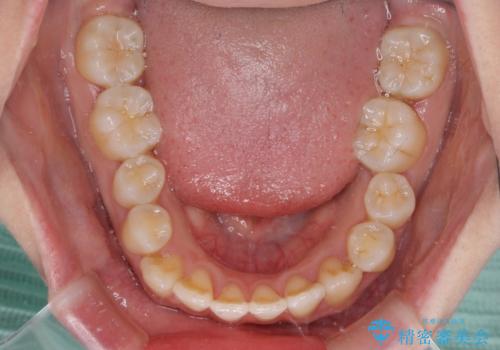

軽微な歯列不正をワイヤー矯正で整える

- 上顎歯列と下顎前歯の叢生を気にして来院された患者様です。

上顎からワイヤー矯正を開始し、終了間際から下顎前歯の叢生解消するよう計画しました。

部分矯正でしたが、咬み合わせに違和感が出ることなく気になる部分を改善させることができました。